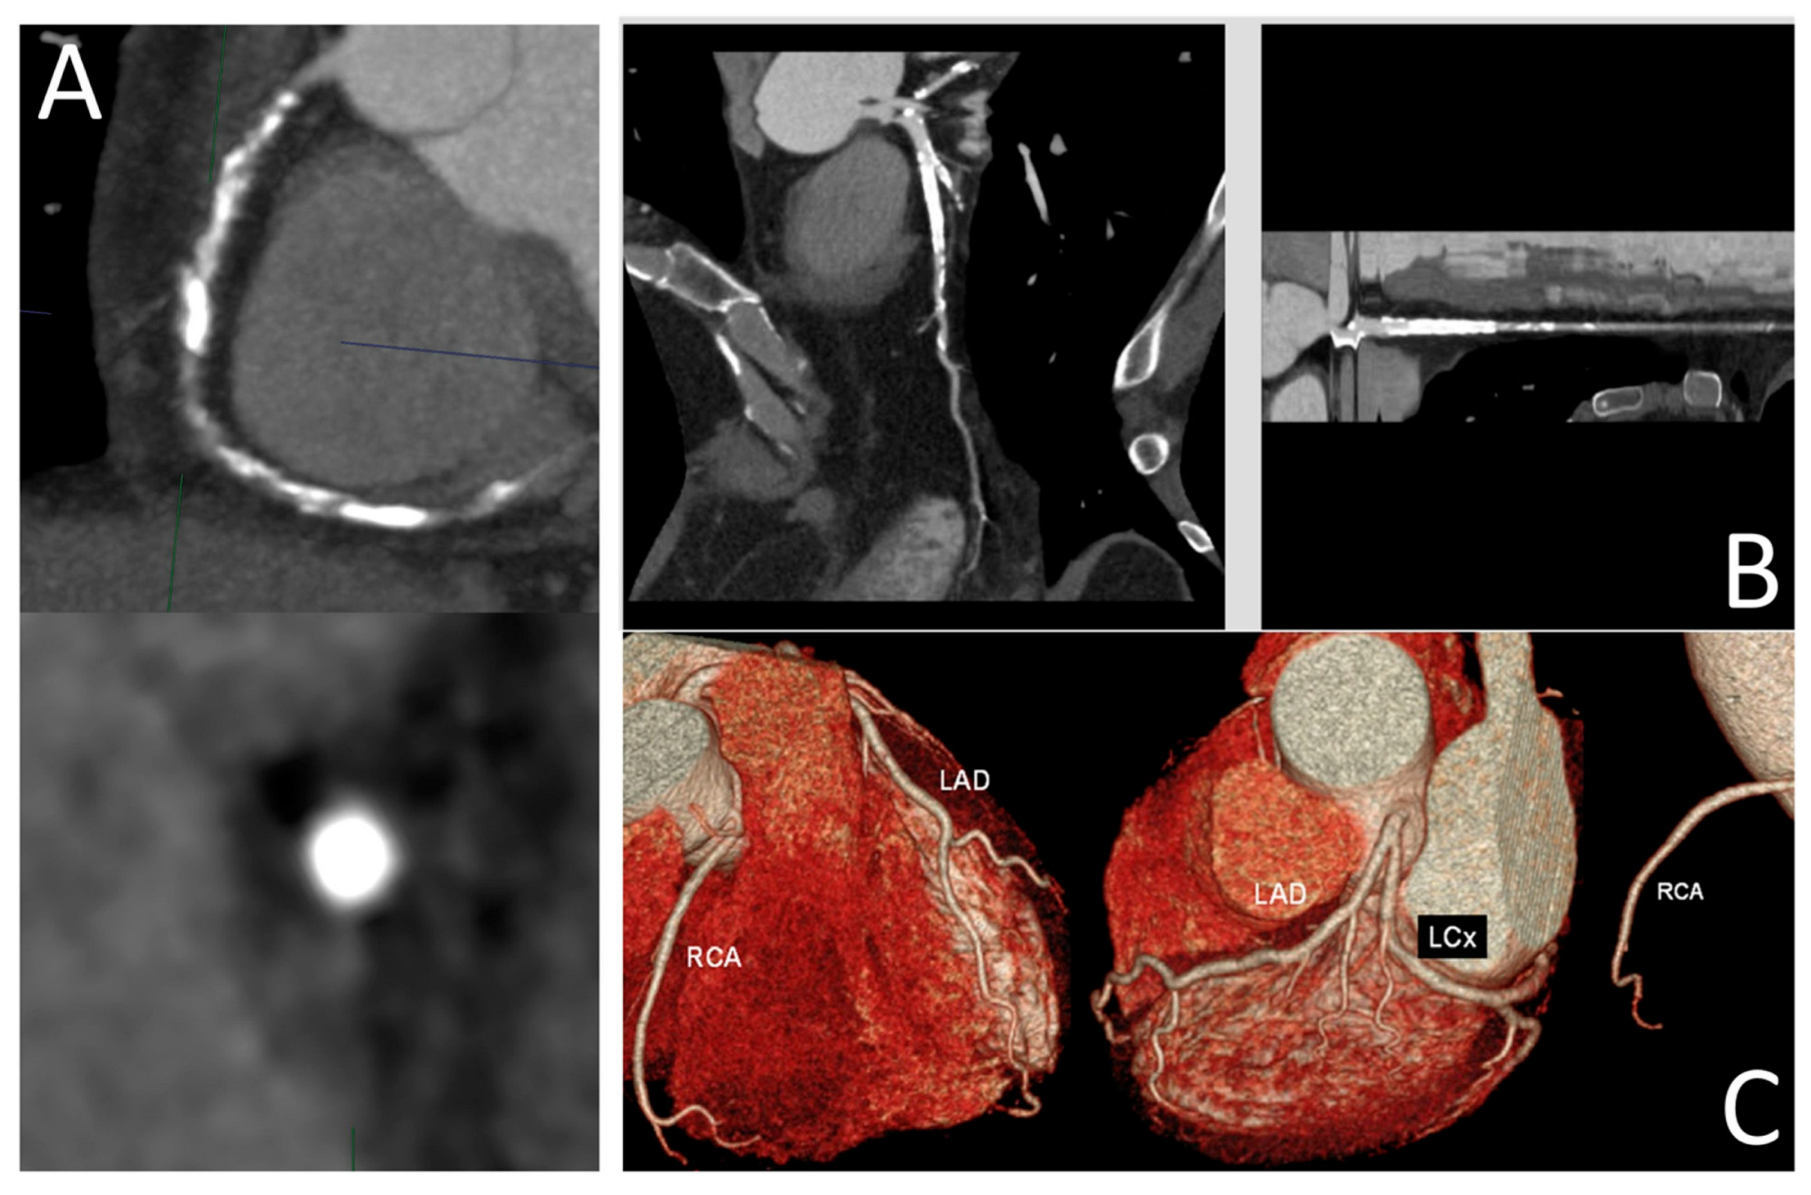

Figure 4. Anomalous aortic origin of the left coronary artery. (Left): Curved multiplanar reformatted coronary CT angiography (CTA) images in a 65-year-old male patient demonstrate severe stenosis at the ostium of the right coronary artery (RCA) and moderate stenosis at the ostium of the left anterior descending (LAD) artery, both originating from the right coronary cusp. (Right): Corresponding fractional flow reserve computed tomography (FFR-CT) images show a value of 0.50 at 2 cm distal to the RCA ostial lesion, indicating significantly reduced flow. The mid LAD displays a value of 0.78, and the distal LAD shows a value of 0.71, suggesting a high likelihood of hemodynamic significance. Based on these findings, the patient proceeded to invasive coronary angiography and subsequent intervention for both lesions. Reprinted with permission under open access from Kasaeian et al. [6].

Kasaeian et al. reviewed the clinical applications of FFR-CT in coronary artery disease [6]. FFR-CT has been increasingly reported in the literature to yield improved accuracy in guiding patient management compared to standard coronary CT angiography (CTA). Real-world evidence of using FFR-CT in clinical practice has been validated by a number of multicenter trials proving that FFR-CT serves as a gatekeeper to invasive coronary angiography by reducing a significant number of unnecessary invasive procedures (Figure 2 and Figure 3). FFR-CT is associated with significantly lower all-cause mortality, so it can guide confidential clinical decision-making. Judicious use of FFR-CT to guide coronary CTA interpretation was discussed alongside distal-to-lesion FFR-CT measurement, showing improved concordance with invasive FFR, hence further enhancing diagnostic precision. In this study, the limitations of FFR-CT are highlighted, along with the impact of high-quality coronary CTA image acquisition and coronary calcium scores on FFR-CT performance. Future potential applications of FFR-CT, such as its implementation in the evaluation of coronary artery anomalies (Figure 4) and plaque characterization, are also reviewed. These authors also reviewed the role of FFR-CT as a reliable tool to plan percutaneous coronary intervention (PCI) and identify suitable patients undergoing coronary artery bypass grafting. Finally, they summarized the role of FFR-CT combined with risk stratification as a gatekeeper to the catheterization lab to reduce unnecessary invasive procedures without comprising clinical outcomes.